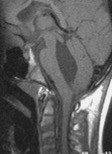

l’engagement tonsillaire

(malformation de Chiari) cf. ci-contre ; classiquement favorisé par le drainage lombo-péritonéal, en fait retrouvé dans l’hyperdrainage par valve ventriculaire.